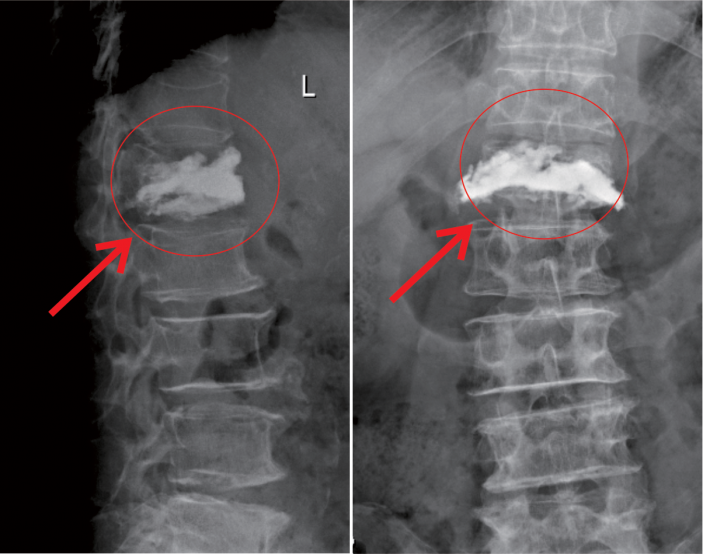

在我院先進的術中三維CT引導下,杜教授确定L1雙側椎弓根進針點,娴熟地将穿刺針穿入L1椎體,經穿刺針建立通道将約11ml骨水泥注入坍塌的椎體中。術中監視,注入的骨水泥逐漸支撐起原本壓縮空洞的椎體。骨水泥凝固後,病變的椎體迅速恢複了承重能力。手術持續約40分鍾,開展非常成功,術後老人的疼痛馬上消失,翻身也無疼痛,第二天就能使用助步器下地行走。

△術前MR顯示,第一腰椎壓縮性骨折

△術後,病變的椎體迅速恢複了功能